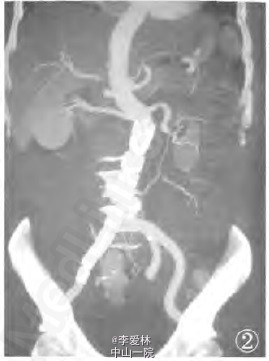

术后1周CTA显示腹主动脉及右髂动脉夹层裂口被完全封闭。夹层动脉瘤内完全血栓形成,患者痊愈出院